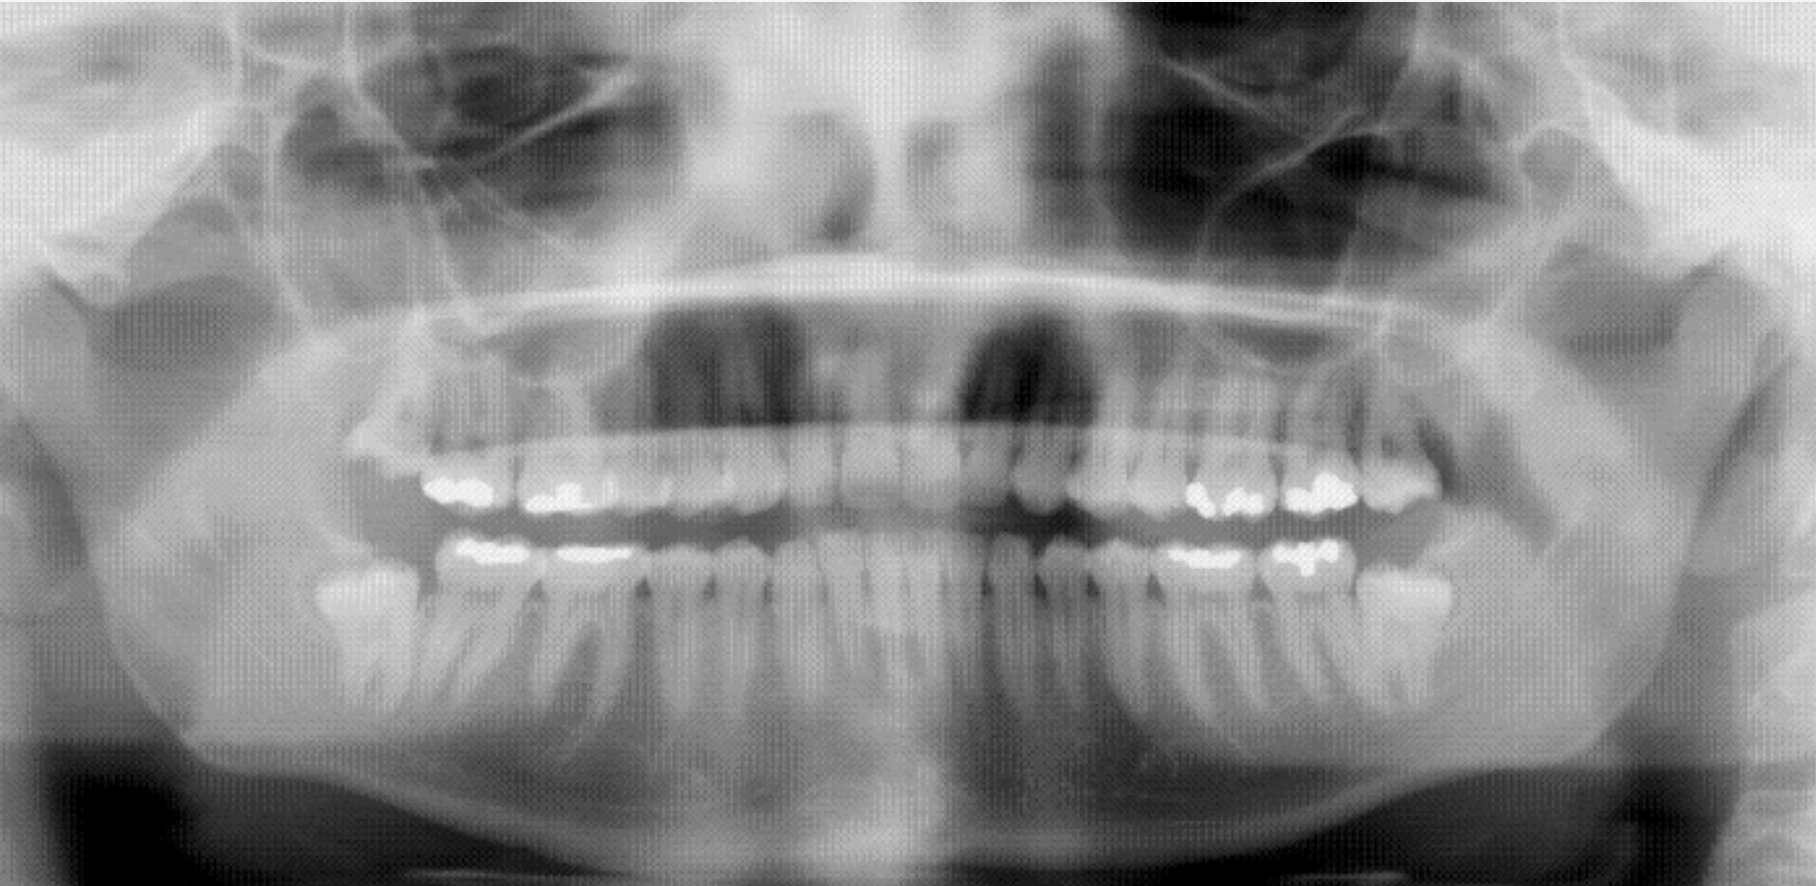

La radiografía panorámica u ortopantomografía representa una imagen general de los maxilares, la mandíbula y los dientes, por lo tanto es de primordial utilidad en el área orofacial.

Su papel de diagnostico odontológico, no sólo de los dientes sino también del maxilar y mandíbula, es fundamental. Sin la ortopantomografía el odontólogo perdería una gran ayuda en la mayoría de las especialidades de su campo. Es utilizada de forma sistemática en odontología, llegando a ser un arma diagnostica rutinaria. El valor diagnóstico de la ortopantomografía en cirugía bucal, implantología ortodoncia, patología oral y dental está claramente demostrado.